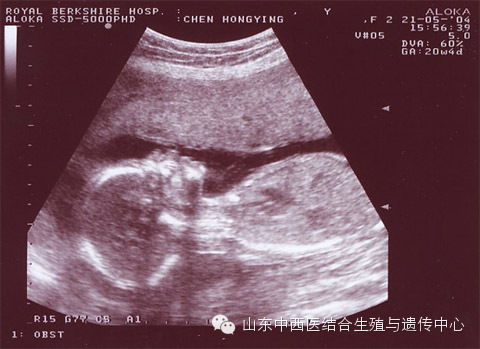

系统B超,又称系统超声筛查,是一种针对孕妇进行全面的胎儿结构畸形筛查的检查方法。它通过高分辨率的超声设备,对胎儿各器官进行细致的观察,以发现潜在的畸形和发育异常。

系统B超的最佳检查时间为怀孕20-26周,尤其是22-24周。这个时期的胎儿大小适中,羊水量充足,有利于获取清晰的图像,提高检查的准确性。

头部:观察胎儿头部结构,如无脑儿、脑积水等。

面部:检查胎儿面部发育,如唇裂、腭裂等。

心脏:观察胎儿心脏结构,如房室间隔缺损、心脏发育异常等。

脊柱:检查胎儿脊柱发育,如脊柱裂等。

四肢:观察胎儿四肢发育,如四肢短小、畸形等。

内脏:检查胎儿内脏器官,如肝脏、肾脏、胃泡等。